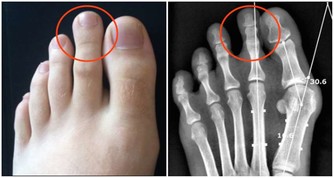

說到痛風,很多人第一印像是膝蓋、腳後跟、腳大拇指等地方疼痛,到醫院一查,尿酸高了!

痛風是由單鈉尿酸鹽沉積所致的晶體相關性關節病,與嘌呤代謝紊亂和(或)尿酸排泄減少所致的高尿酸血症直接相關,特指急性特徵性關節炎和慢性痛風石疾病。

主要包括急性發作性關節炎、痛風石形成、痛風石性慢性關節炎、尿酸鹽腎病和尿酸性尿路結石,重者可出現關節殘疾和腎功能不全。

痛風是長期嘌呤代謝障礙,導致體內長期尿酸增高,會在局部形成尿酸結晶,特別是下肢的足背小關節,會導致痛風性關節炎,或是直接形成痛風石,從而會刺激關節面引起反复的疼痛。其臨床特點就是高尿酸血症。但在疼痛急性發作期並不一定的尿酸最高時。